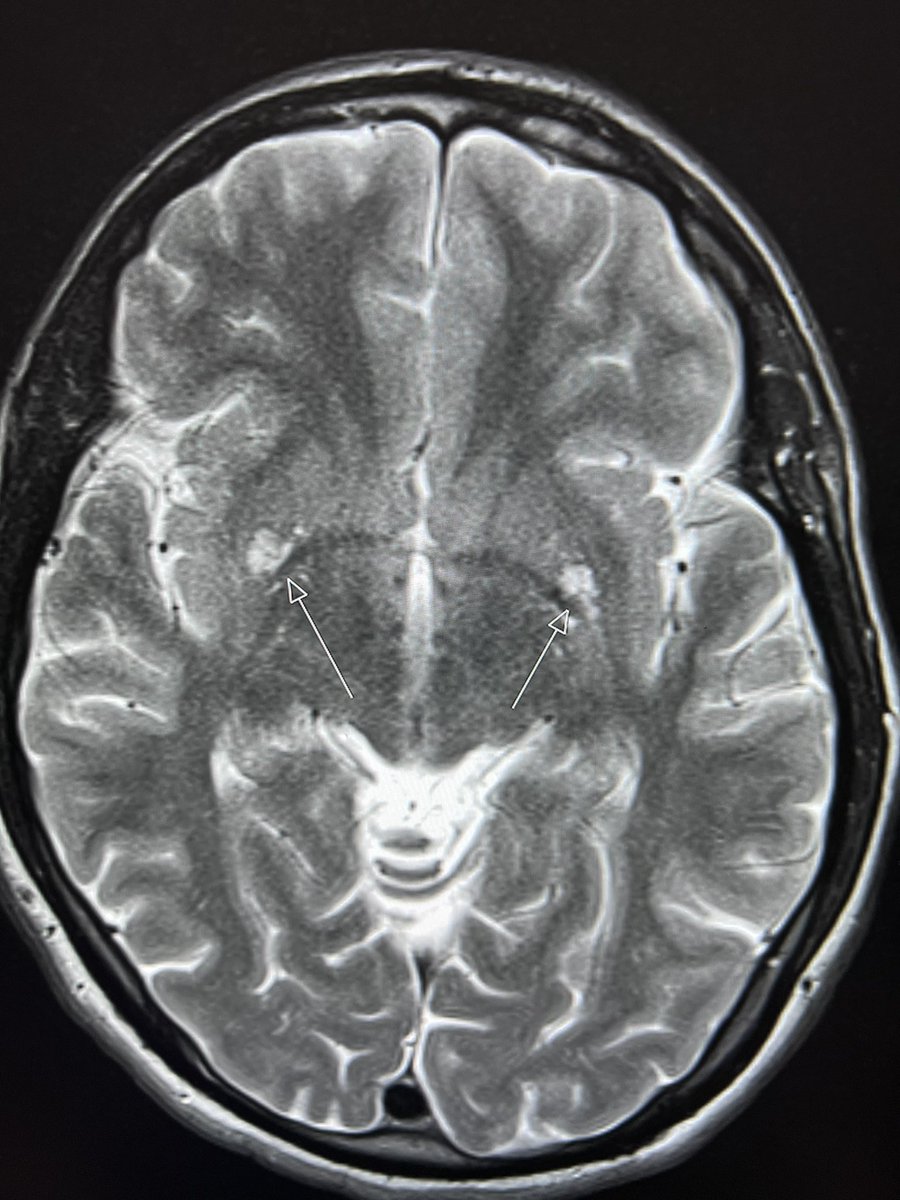

I've presented an EPoster about the improvement in the sensory function in mouse treated with iron-free transferrin in experimental ICH.